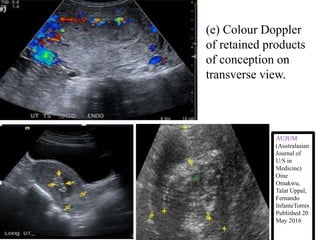

(e) Colour Doppler

of retained products

of conception on

transverse view.

AUJUM

(Australasian

Journal of

U/S in

Medicine)

Oine

Omakwu,

Talat Uppal,

Fernando

InfanteTorres

Published 20

May 2016

(e) Colour Doppler ofretained products of conception on transverse view. AUJUM (Australasian Journal of U/S in Medicine) Oine Omakwu, Talat Uppal, Fernando InfanteTorres Published 20 May 2016